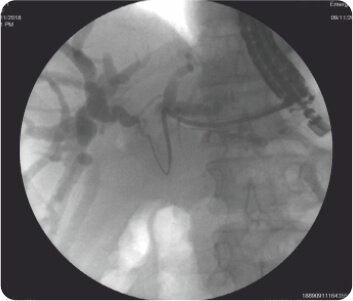

লিভারের দ্বিতীয় অংশে IHBRD এর EUS নির্দেশিত পাংচার পাকস্থলী থেকে করা হয়েছিল এবং কোলাঞ্জিওগ্রামের পরে, সিস্টোটোম ব্যবহার করে ট্র্যাক্টটি 10F পর্যন্ত ধারাবাহিকভাবে প্রসারিত করা হয়েছিল এবং পেট এবং লিভারের দ্বিতীয় অংশের সাথে সংযোগকারী একটি 60×10 মিমি সম্পূর্ণরূপে আবৃত বিলিয়ারি ধাতব স্টেন্ট স্থাপন করা হয়েছিল। ধাতব স্টেন্টের স্থানচ্যুতি রোধ করার জন্য ধাতব স্টেন্টের ভিতরে একটি 7F 7 সেমি ডাবল পিগটেল প্লাস্টিক স্টেন্ট স্থাপন করা হয়েছিল। কোনও পেরিপ্রোসিডেরাল জটিলতা ছিল না এবং বিলিরুবিনের স্বাভাবিকীকরণের পরে রোগীকে কেমোথেরাপি করা হয়েছিল। পদ্ধতির 3 মাস পরে ফলো-আপের সময়, রোগীর LFT স্বাভাবিক ছিল।

চোলাঞ্জিওগ্রাম